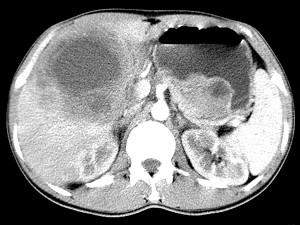

问题 女,61岁,上腹部疼痛一个月,食欲减退,消瘦,CT所见如图,最可能的诊断是 ( )

选项 A、肝包虫病 B、原发性肝癌 C、肝转移瘤 D、胃癌肝转移 E、肝脓肿

答案 D